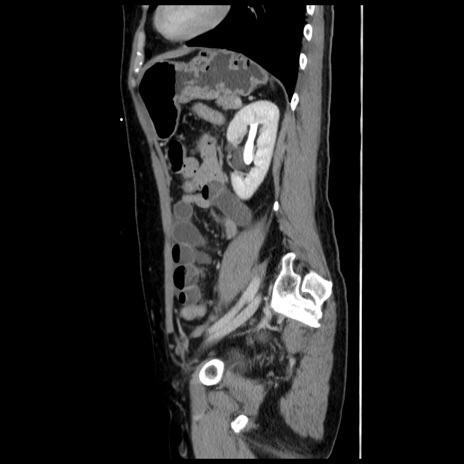

横断像

【症例】 50歳代女性

【主訴】 腹痛

【現病歴】前日生レバーを食べた。今朝に排便あり。 昼前に突然発症の腹痛を生じ、当院救急外来を受診した。

【既往歴】 子宮筋腫にてで子宮全摘後

【身体所見】 意識清明、腹部:平坦、軟、下腹部やや左を中心に圧痛・反跳痛あり、筋性防御あり

【データ】WBC 7800、CRP 0.07